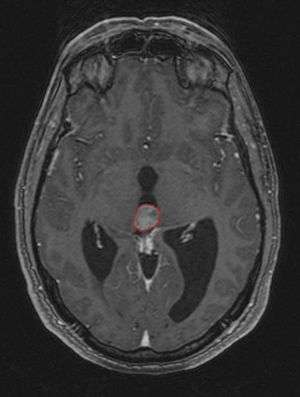

Frequently, paralysis of upward gaze along with several ocular findings such as convergence retraction nystagmus and eyelid retraction also known as Collier's sign and Light Near Dissociation (pupil accommodates but doesn't react to light) are known collectively as Parinaud's syndrome [1] or Dorsal Mid-brain syndrome, are the only physical symptoms seen. This is caused by the compression of the vertical gaze center in the midbrain tectum at the level of the superior colliculus and cranial nerve III. Work-up usually includes Neuro-imaging as seen on the right.